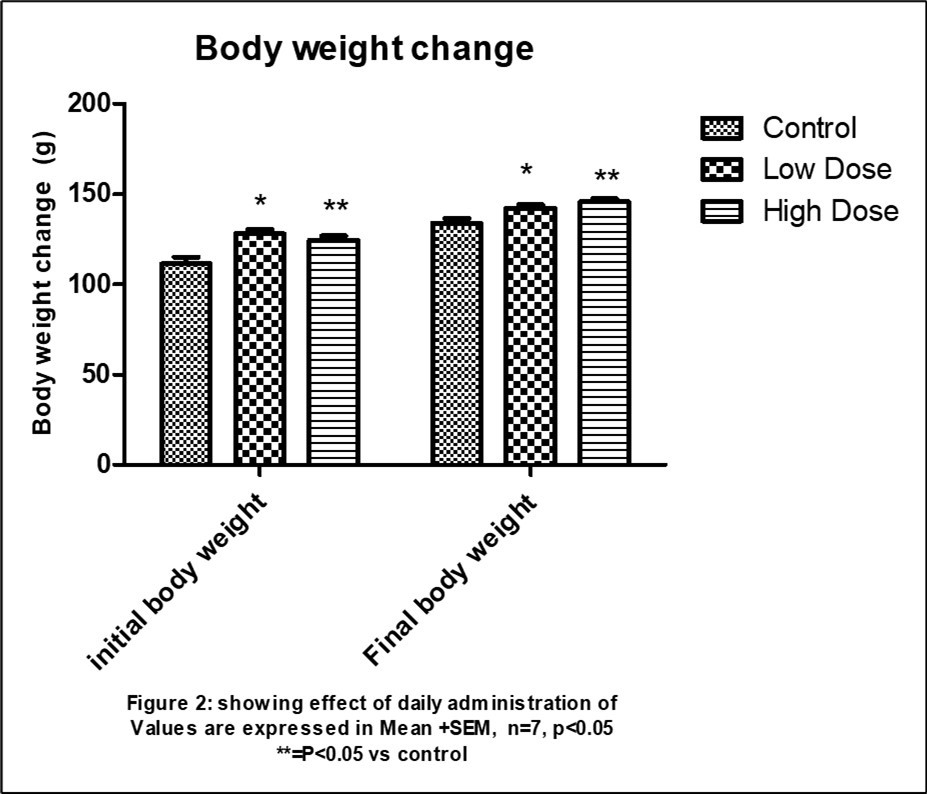

Morphological observation from the study shows an observable significant (p<0.05) increase in the final mean body weight when compared with the initial body weight observable in control vs low dose, control vs high dose and low dose vs control but not observable in low dose vs high does and high dose vs control dose. The final body weight of the control animals (133.9 ± 7.058) was significantly (p<0.05) higher than its initial body weight (111.4 ± 8.162). however, the mean final body weight of the low dose group (142.3 ± 4.716) and high dose group (145.7 ± 4.786) were significantly (p<0.05) higher than their initial body weights (128.0 ± 6.856) and (130.3 ± 6.157) respectively. Table 1, Figure 1

Figure 1.Effect of daily administration on body weight

| GROUPS | INITIAL | FINAL |

| Control | 111.4 ± 8.162 | 133.9 ± 7.058 |

| Low dose | 128.0 ±6.856 | 142.3 ± 4.71 |

| High dose | 130.3 ± 6.157 | 145.7±4.786 |

Since prehistoric times, therapeutic plants, often known as medicinal herbs, have been identified and employed in traditional medicine practices. Plants synthesis hundreds of chemicals compounds for functions including defence against insects, fungi, diseases and herbivorous animals, numerous phytochemicals with potential or established biological activity have been identified. Further the phytochemical contents and pharmacological actions, if any, of many plants having medicinal potentials remain unassessed by rigorous scientific research to define efficacy and safety 25. The World consumption of medicinal plants is growing rapidly. The need to verify claims of medicinal properties as well as determine their safety limits cannot be overemphasized. Usage of herbal preparations without control dosage coupled with non-availability of adequate scientific studies on their safety has raised concerns on their toxicity 26. Morphological findings from this present study, showed that there was a significant increase in the final body weights of rats treated with high and low doses of Albemoschus Esculentus extract when compared to rats in the control group. This is in conformity with previous studies by some authors reporting that the administration of abelmoschus esculentus causes increase in body weights of treated rats 27, 28, 29.

The significant increase in body weight may be due to the fact that, abelmoschus esculentus contains essential minerals, vitamins, lipids, amino acids including lysine and tryptophan and as well as proteins which are very vital for animal growth 30, 31, 32.